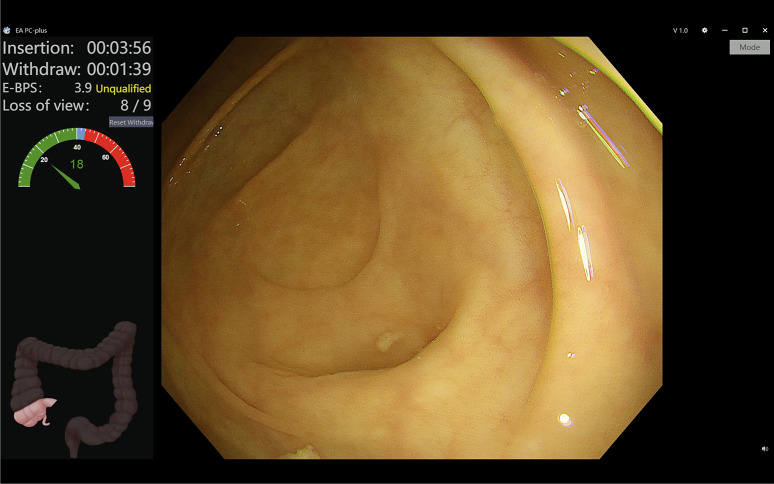

结肠镜检查在降低结直肠癌发病率和死亡率方面具有至关重要的作用。开发不同的人工智能(AI)系统,进一步提高其质量保证(计算机辅助质量改进,CAQ),病变检测(计算机辅助检测,CADe)和病变表征(计算机辅助表征,CADx)。有研究调查了这些人工智能系统在标准结肠镜检查的不同领域中的作用。方法:在这篇最新的叙述性综述中,我们总结了目前的证据,讨论了现有的局限性,并探讨了人工智能在结肠镜检查中的未来发展方向。结果:CAQ通过实时反馈和质量监测系统提高结肠镜检查质量,但由于训练数据集较小和方法不同,研究结果不一致。CADe提高了腺瘤的检出率,降低了腺瘤的漏检率,但也存在假阳性、不必要的息肉切除术、潜在的内窥镜医师技能下降和成本效益等问题。CADx系统在区分息肉类型方面的结果和准确性参差不齐,其使用进一步受阻于对无梗锯齿状病变的不充分代表,以及缺乏与标准结肠镜检查进行比较的严格试验。结论:尽管人工智能辅助结肠镜检查的证据越来越多,但其潜在的缺陷和局限性可能会阻碍其在实际临床实践中的进一步实施。关于临床疗效、成本效益、责任和数据共享的长期数据是需要解决的关键领域。

Results: CAQ enhances colonoscopy quality through real-time feedback and quality monitoring systems, but the studies have inconsistent results due to small training datasets and varied methodologies. CADe increases adenoma detection rate and reduces adenoma missed rates, but there are concerns about false positives, unnecessary polypectomies, potential deskilling of endoscopists, and cost-effectiveness. CADx systems have mixed results and accuracies in differentiating polyp types, and its use is further hindered by inadequate representation of sessile serrated lesions and a lack of rigorous trials comparing it with standard colonoscopy.